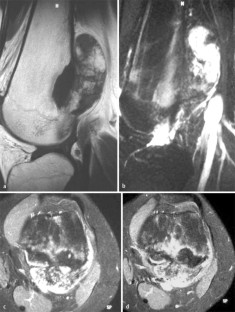

MRI morphology of bone tumors and tumor-like lesions

Für das Staging und die Charakterisierung von Knochentumoren und tumorähnlichen Läsionen ist in der Magnetresonanztomographie (MRT) der Einsatz von Spinechosequenzen erforderlich. Die MRT hat nur einen geringen Stellenwert in der Bestimmung der Dignität. Obwohl viele Knochentumoren und tumorähnliche Läsionen eine vergleichbare Morphologie in dieser bildgebenden Modalität aufweisen, können einige Tumorentitäten mittels MRT recht zuverlässig diagnostiziert werden. Hierzu zählen Knorpeltumoren, die solitäre und aneurysmatische Knochenzyste, der Riesenzelltumor, fetthaltige Läsionen und bis zu einem gewissen Grad auch das Osteoidosteom und das Osteoblastom. Es werden praktische Tipps gegeben, wann bei Tumorverdacht die MRT eingesetzt werden sollte, wie bei einem zufällig bei einer MRT gefundenen Tumor die Untersuchung modifiziert werden sollte und welcher Tumor vorliegen könnte.

Spin-echo sequences are mandatory at MRI for staging and characterization of bone tumors and tumor-like lesions. MRI is of minor value in the estimation of the malignant potential of an osseous lesion. Although many bone tumors and tumor-like lesions present similar morphology at MRI, some entities can be diagnosed with good reliability. These include chondrogenic tumors, solitary and aneurysmal bone cysts, giant cell tumors, lesions containing fatty tissue and, to a certain extent, osteoid-osteomas and osteoblastomas. Practical advice is given regarding when to perform a MRI study in cases of tumor suspicion. Further advices are given for cases a tumor is found incidentally at a MRI study, how to modify the study and which kind of tumor may be present.